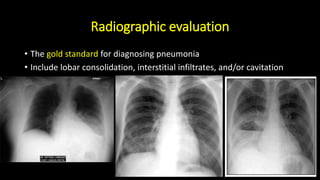

Radiographic evaluation

• The gold standard for diagnosing pneumonia

• Include lobar consolidation, interstitial infiltrates, and/or cavitation